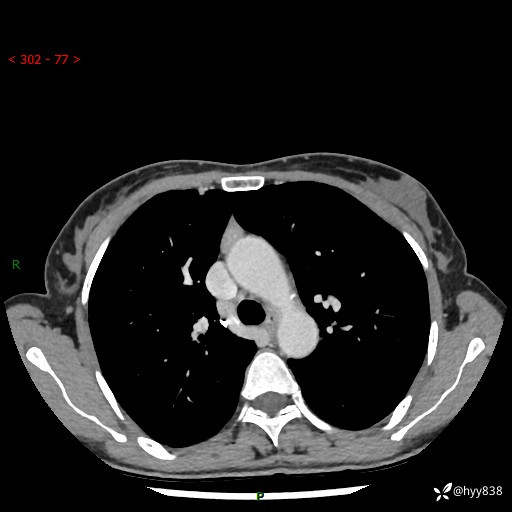

偶然发现纵隔占位,如何解读CT“结中结”---结果公布~

主诉:上腹部不适7天,CT偶然发现纵隔占位

临床诊断:纵隔占位

胸部CT平扫

增强动脉期+静脉期